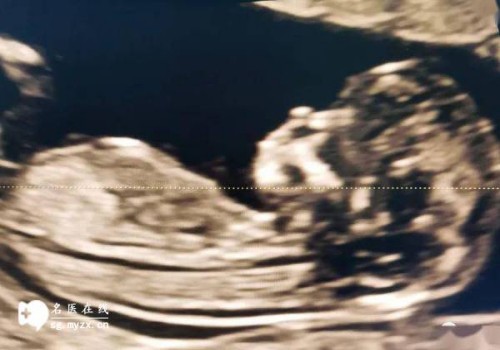

- 1、胎儿因素:大概占到流产原因的40%-50%,其中大部分是胎儿自身染色体的异常,或者某些基因片段异常,可以通过流产组织中的绒毛进行DNA检测或者染色体培养得出结论;